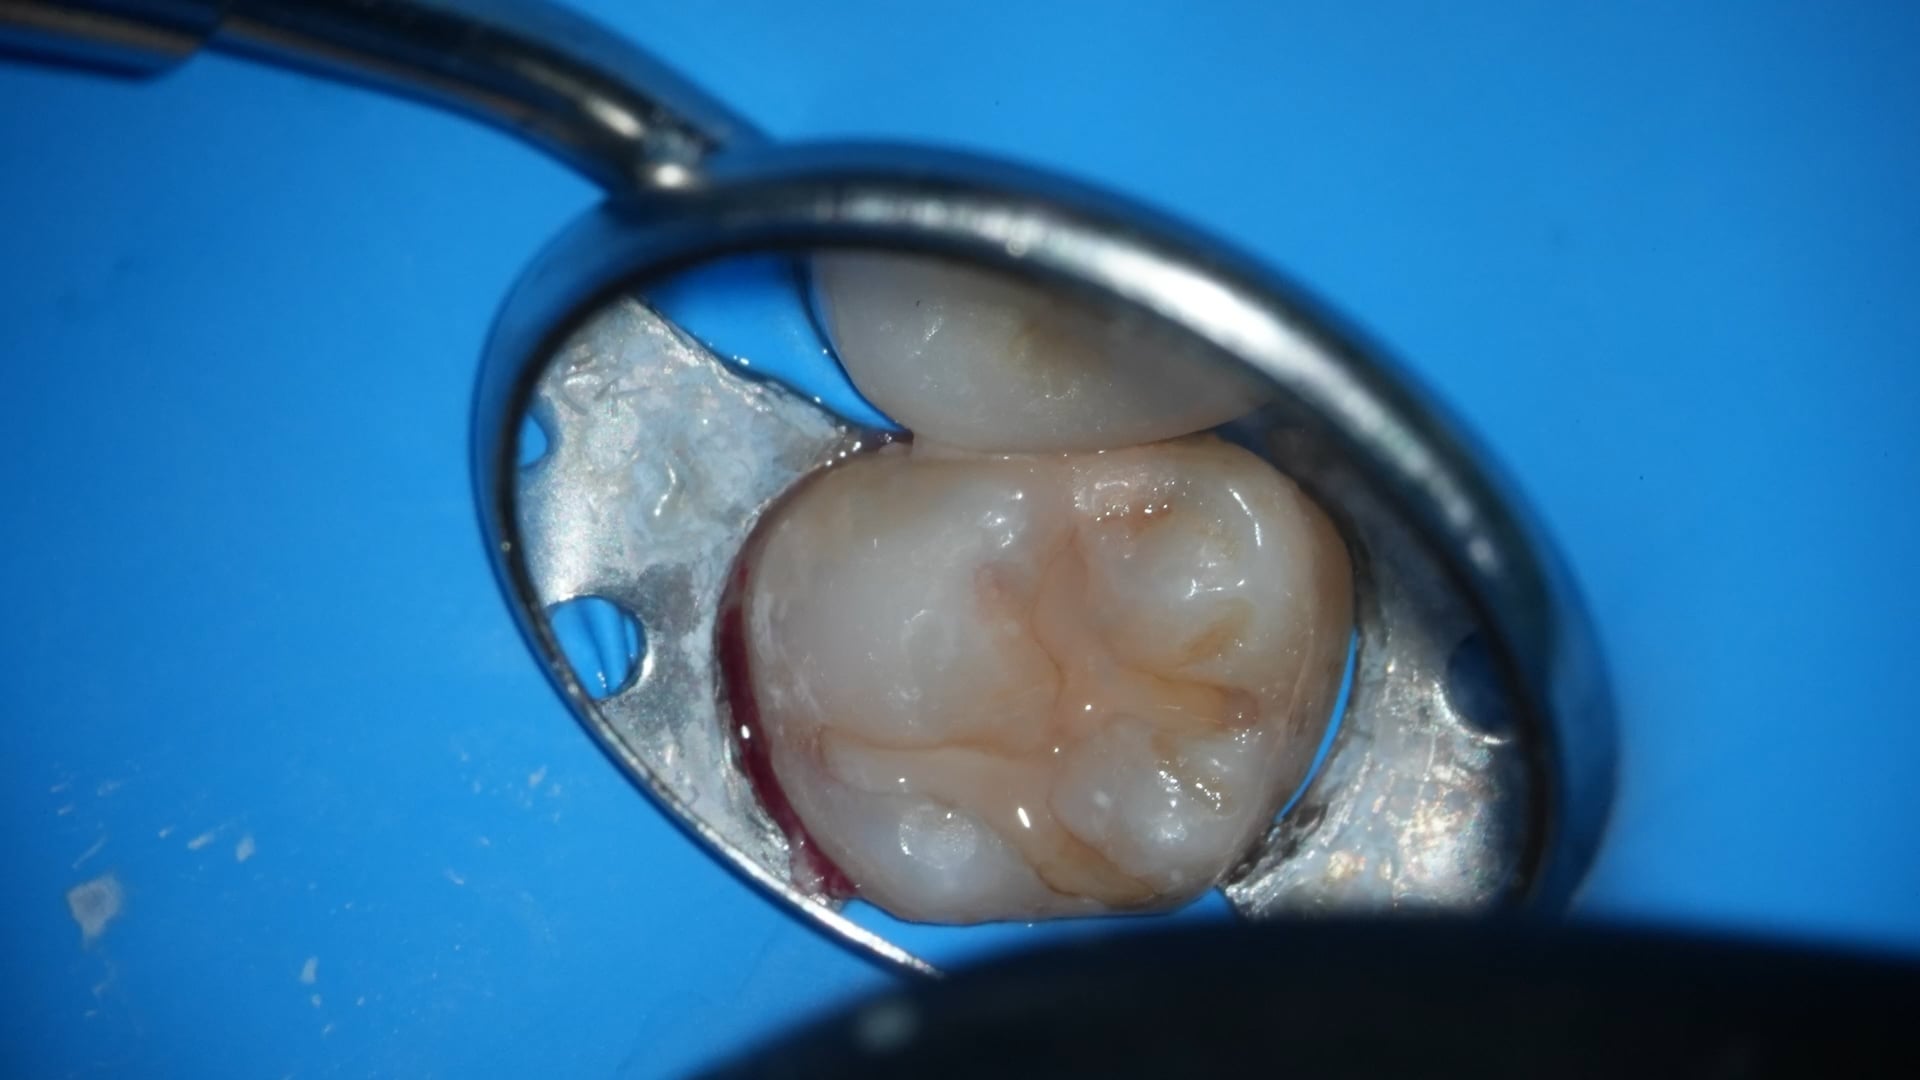

研磨

歯間離開器を外した状態で隣接面を確認する。隣接面や充填周囲はNo12のメスで成形することで、天然歯を傷つけずに余剰なレジンだけを削除できる。

• Point

術後